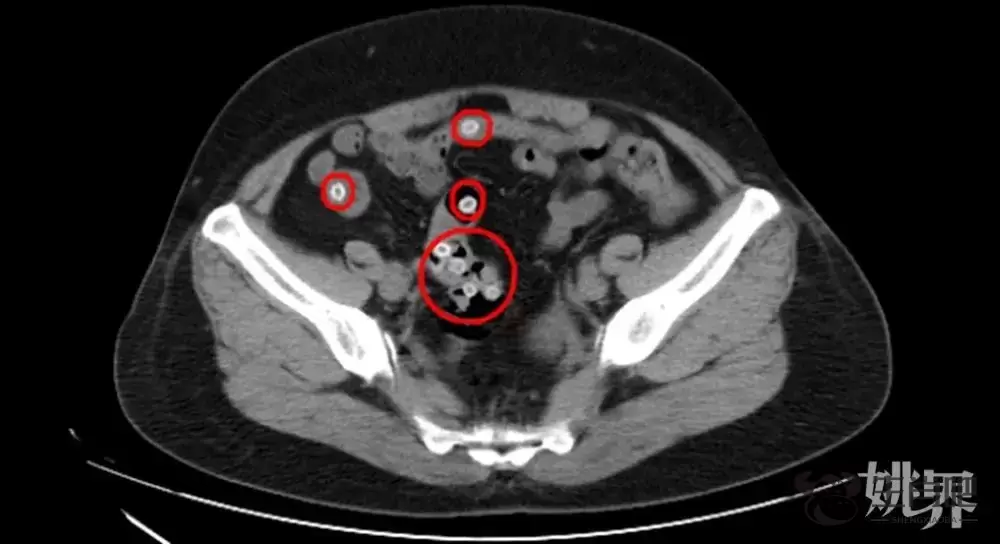

CT影像显示,患者肠道内有不少杨梅核滞留

CT影像显示,王阿姨的肠内存在多处类圆形高密度影,密密麻麻的圆圆小白点正是滞留在肠道内的杨梅核,这是导致患者腹痛不止的罪魁祸首。